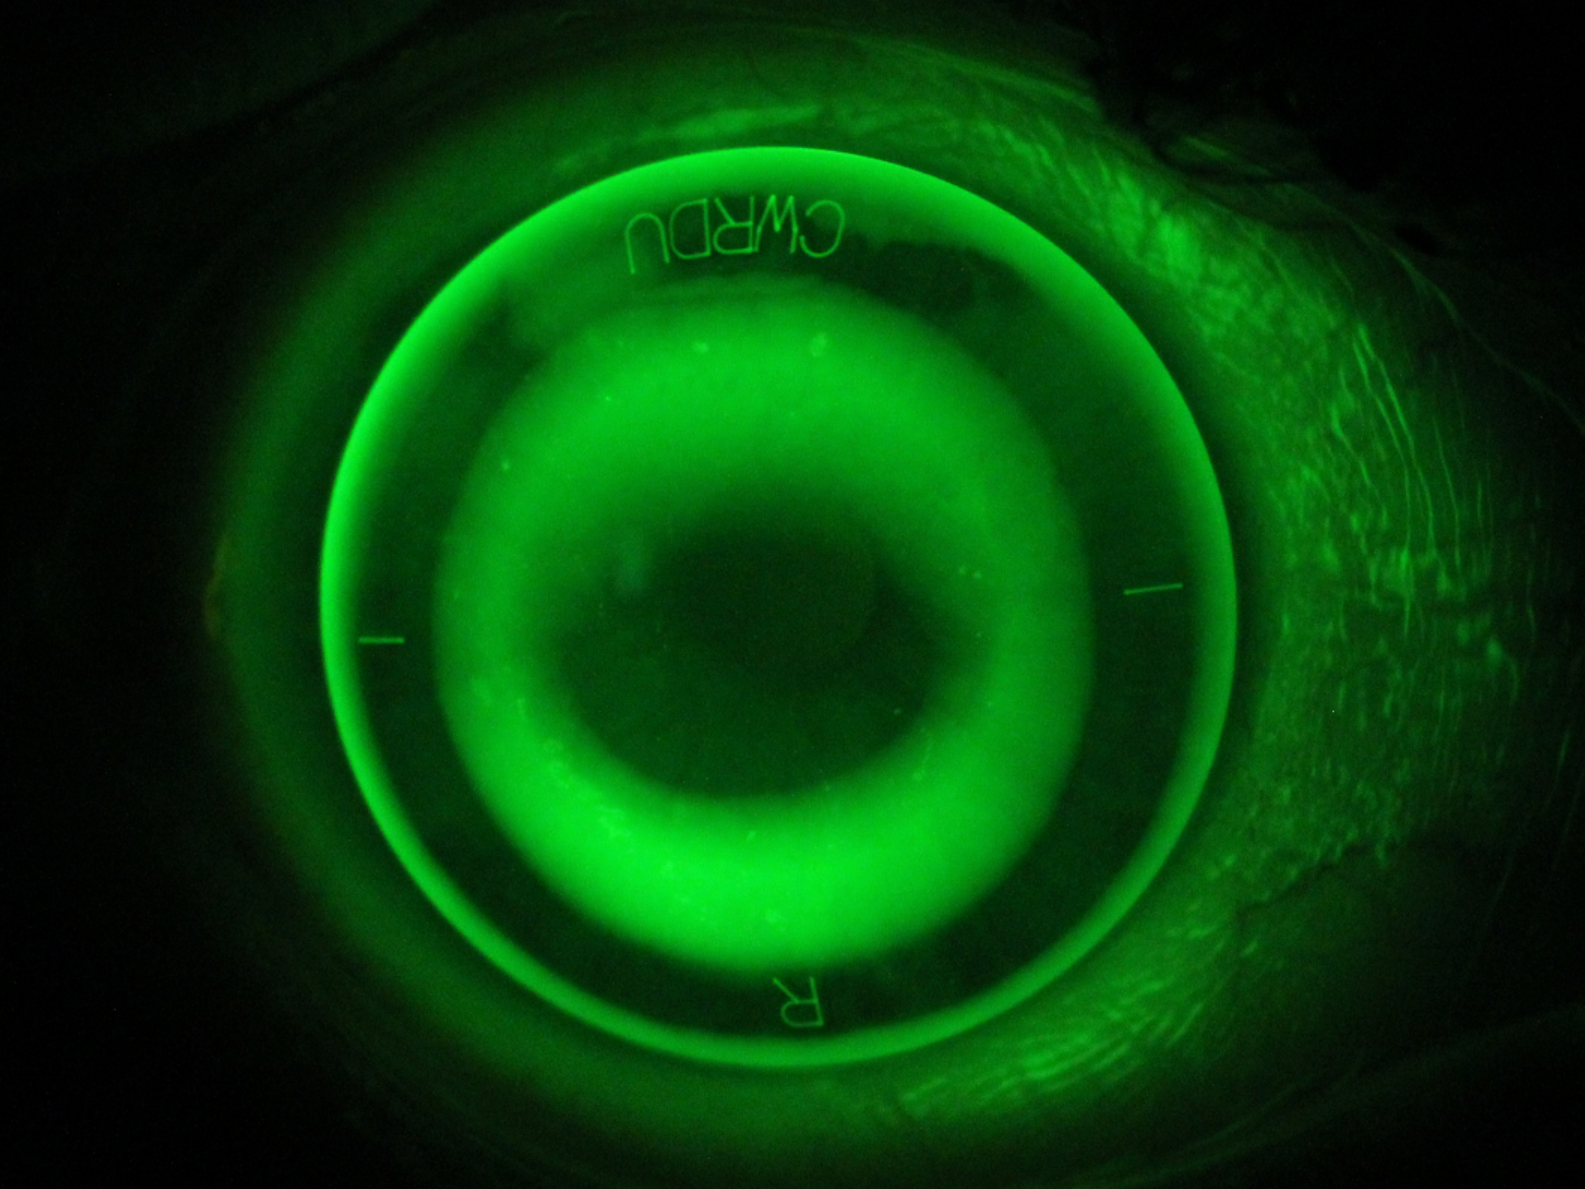

Orthokeratology (Ortho-K) is a safe, non-surgical treatment where specially designed contact lenses temporarily reshape the front of your eye (cornea). This provides crisp daytime vision and can also help to slow the progression of myopia (short-sightedness).